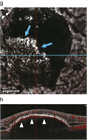

1. 新生血管型AMDは、MNVの存在する位置(深さ)で分類し、MNVがRPE下に存在すれば1型MNVで、1型MNVの端部にポリープ状病巣がみられればポリープ状脈絡膜血管症(polypoidal choroidal vasculopathy:PCV)である。わが国の新生血管型AMDの半数以上がPCVである。RPE上から網膜下に存在すれば2型MNV、混在するものは1+2型MNVである。網膜血管から生じたMNVは3型MNVで、網膜血管腫状増殖(retinal angiomatous proliferation:RAP)とも呼ばれる[3]